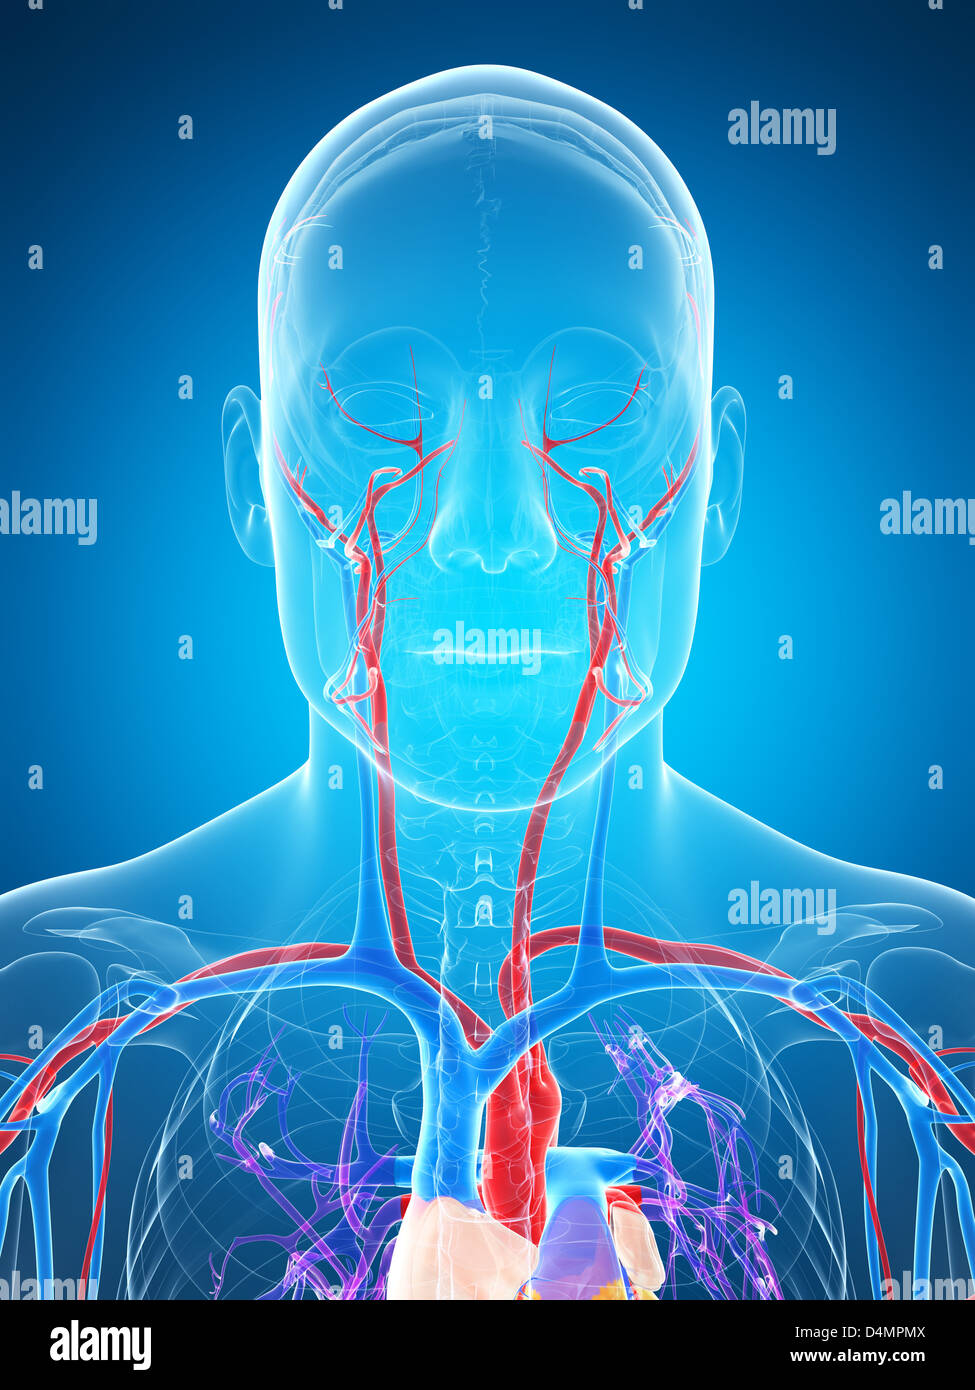

Vascular system Stock Photohttps://www.alamy.com/image-license-details/?v=1https://www.alamy.com/stock-photo-vascular-system-54546602.html

Vascular system Stock Photohttps://www.alamy.com/image-license-details/?v=1https://www.alamy.com/stock-photo-vascular-system-54546602.htmlRFD4MPMX–Vascular system

Vascular system Stock Photohttps://www.alamy.com/image-license-details/?v=1https://www.alamy.com/stock-photo-vascular-system-54568462.html

Vascular system Stock Photohttps://www.alamy.com/image-license-details/?v=1https://www.alamy.com/stock-photo-vascular-system-54568462.htmlRFD4NPHJ–Vascular system

Vascular system Stock Photohttps://www.alamy.com/image-license-details/?v=1https://www.alamy.com/stock-photo-vascular-system-54568186.html

Vascular system Stock Photohttps://www.alamy.com/image-license-details/?v=1https://www.alamy.com/stock-photo-vascular-system-54568186.htmlRFD4NP7P–Vascular system